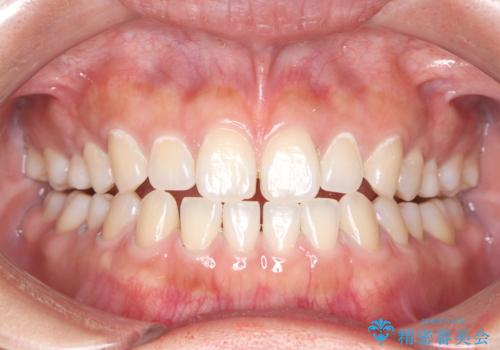

エアフローでステイン除去!

- メンテナンスの際に歯のステインが気になるということで今回はエアフローの機械を使用したクリーニングを行いました。

ステインが付着したままだと歯の表面がざらつき、普段のブラッシング時などに汚れが落ちにくくなります。定期的なメンテナンスの際にPMTC、エアフローを取り入れることをおすすめしております。